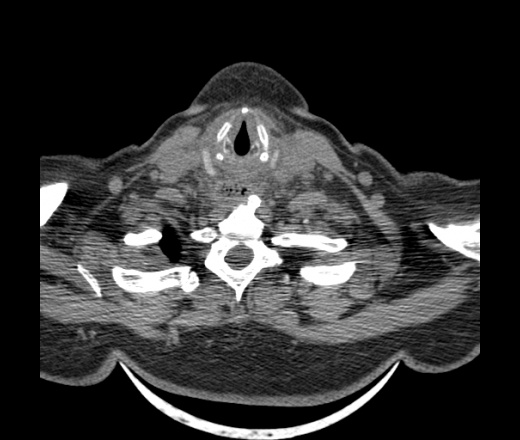

Женщина поступила в х/о спустя 4 дня после того как при употреблении карася подавилась костью.

Наличие газа в средостении на протяжении тел С2-С6 (медиастинальна эмфизема); рыбная кость на уровне тела С6.

При всем уважении, но говорить о медиастинальной эмфиземе, оценивая мягкие ткани шеи, как-то слишком резко. На мой взгляд, это ретрофарингеальное пространство.

Эвакуировали почти 100мл гноя. Но кость не смогли найти. Думаю что она даст дальнейшее ослоднение. Эндоскопически за черпалонадгортаной звязкой не смогли зайти в пищевод, все мягкие ткани отечные, просвет пищевода сдавлен. По всей видимости параэзофагеальная клетчака тоже задействована. Эмпиема, если ее можно так назвать, незнаю как правильно дошла до уровня яремной вырезки. Чем закончиться напишу. Ждем медиастинита.

Согласен с Вами; конечно, наличие газа в клетчатке ретрофарингеального пространства (затмение с опечаткой..). К сожалению, процесс "продвигается" к медиастиниту. Но почему никто, не отмечает наличие рыб. кости; или это для Всех очевидно?

Кость то мы сразу выявили, размеры где то 17*2мм, но ее так и не получается найти в этой каше